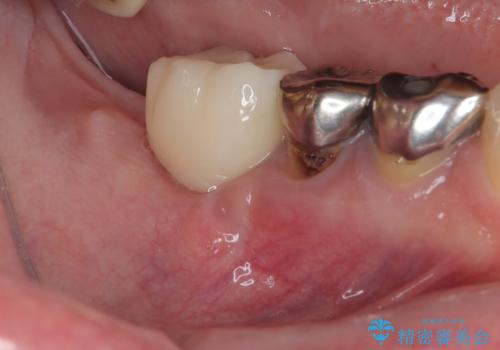

- 「歯を抜いたので、インプラントを入れてほしい」という主訴で来院された患者様です。

他院で歯根破折により抜歯をしたとのことでした。

CTにより残存骨量を確認しインプラント埋入を行っていくこととしました。

今後手前の根管治療を行っている歯が歯根破折を起こして抜歯になる可能性を想定して手前の歯に平行にインプラント埋入を行っています。